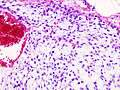

Histopathologic image of chondrosarcoma of the chest wall. Surgical resection of recurrent mass. H & E stain.

Chondrosarcoma is a cancer composed of cells derived from transformed cells that produce cartilage.[1] Chondrosarcoma is a member of a category of tumors of bone and soft tissue known as sarcomas. About 30% of skeletal system cancers are chondrosarcomas.[2] It is resistant to chemotherapy and radiotherapy. Unlike other primary bone cancers that mainly affect children and adolescents, chondrosarcoma can present at any age. It more often affects the axial skeleton than the appendicular skeleton.[3]

Physicians grade chondrosarcoma using several criteria, but particularly on how abnormal the cancerous cells appear under the microscope, and the growth rate of the tumors themselves, both of which are directly linked to the propensity of the cancer to invade locally, and to spread widely to distant organs and sites in the body (called metastasis).

Grade 1 chondrosarcoma grows relatively slowly, has cells whose histological appearance is quite similar to cells of normal cartilage, and have much less aggressive invasive and metastatic properties. Grades 2 and 3 are increasingly faster-growing cancers, with more varied and abnormal-looking cells, and are much more likely to infiltrate surrounding tissues, lymph nodes, and organs. Some, but not all, authorities and medical facilities assign a "Grade 4" to the most anaplastic, undifferentiated cartilage-derived tumors.